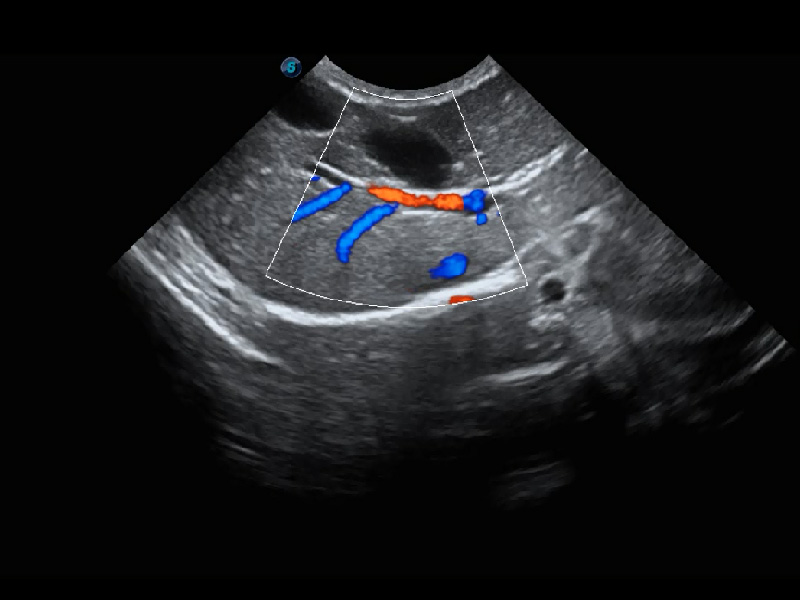

ProPet 60 作為一款高端臺(tái)式動(dòng)物超聲設(shè)備,為動(dòng)物醫(yī)生的日常診斷提供了一系列貼合動(dòng)物臨床需求、解決臨床實(shí)際問(wèn)題的高級(jí)成像功能。憑借全系列高清探頭,滿足醫(yī)生對(duì)腹部、心臟、生殖、淺表、肌骨等成像的所有需求,切實(shí)幫助您提升檢查效率,提高診斷信心。